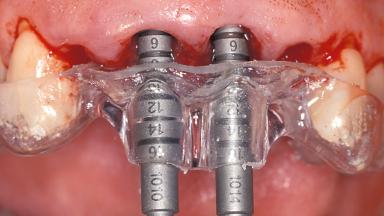

Replacement of the Four Maxillary Incisors with a Fixed Dental Prosthesis Using an Immediate Loading Protocol

# of Implants 2

Type of Implants One-Piece

Guided Surgery No

Loading Protocol Immediate